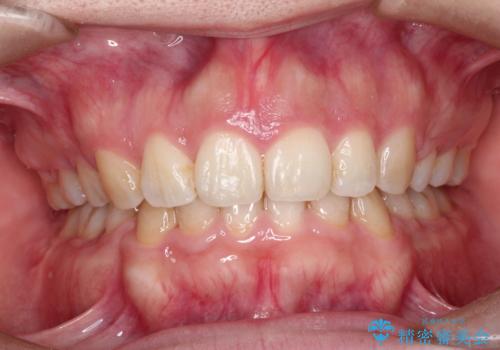

右上の歯は、歯並び的には前から4番目の歯を抜歯したかったのですが、5番目の歯がすでに治療してある歯でしたのでこちらの歯を抜歯しました。

これにより少し治療期間が延びてしまいましたが、健康な歯を残すことができました。

口元もすっきりとすることがで、口も自然に閉じるようになりました。